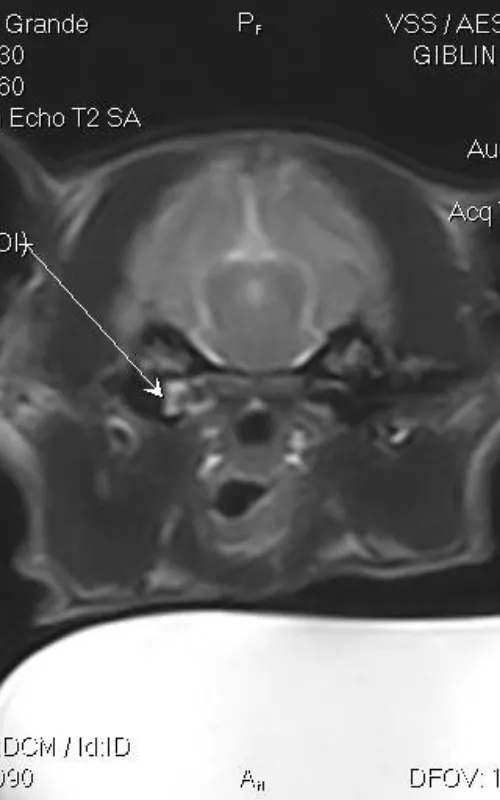

Over several visits, Rusty underwent a combination of diagnostic investigations and interventions, including CT imaging, nasal flushes, deep swabbing and culture-guided antimicrobial therapy. Supportive care has included nebulisation, anti-inflammatories and mucolytics. Because Rusty’s response has varied over time, we’ve had to make adjustments to his care as his needs change.